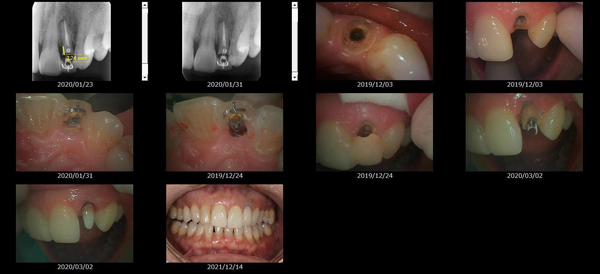

救歯MTM

虫歯が大きくて残せない歯、転倒などの事故により歯が根の深いとこで折れてしまったなどで、抜かざるを得ない歯を、骨の中に埋まっている健全な根を、骨の上に矯正的に引き上げることで、その歯を抜かず温存、救歯できる可能性のある治療方法です。

この特別な診療である救歯MTMは、以下のような特徴があります。

①健全な歯を、歯肉から見える位置にまで引き上げることで

根の治療の成功率を上げることが出来る。唾液には沢山の細菌がいます。唾液が入らない環境での根の治療を(神経の治療)を行うことで神経の治療、根の治療の成功率は格段と上がります。

②骨の上にある歯と土台で支える被せもの製作できる。

被せものを土台だけに頼ることなく、引き上げた健全な歯でも支えることで、歯への被せ物がしっかりと装着できるようになる。

③抜かずに歯を活かすことで、隣の歯を削るブリッジやインプラントにしないで済むことがある。

歯を矯正的に引き上げることで、その歯を救歯できるだけでなく、隣の歯を削るなどの侵襲を回避できる場合がある。

救歯治療と審美性の両立

当院では様々な治療の基礎に審美と機能の両立というテーマがあります。

症例

-